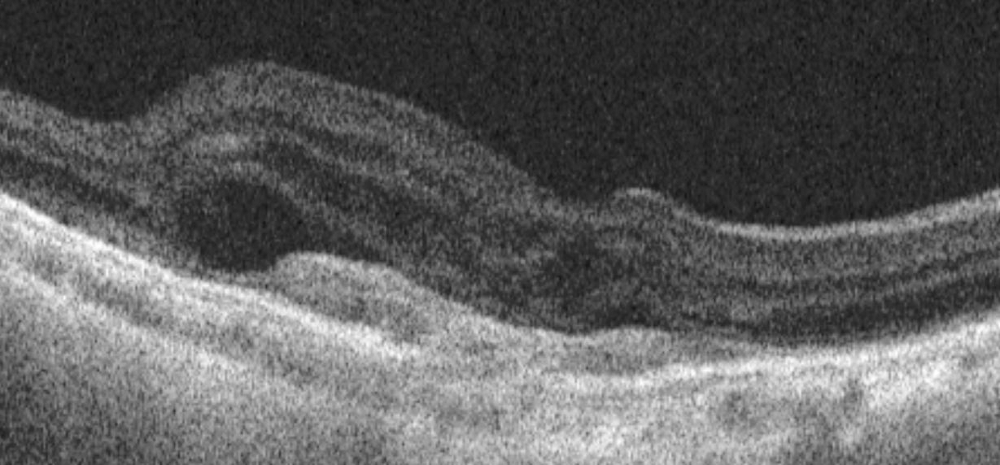

Imagem de tomografia de coerência óptica mostrando lesão hiper-refletiva na camada retiniana externa, fluido sub-retiniano e intrarretiniano

Do acervo de Sajjad Mahmood MA, MB BCHIR, FRCOphth; usado com permissão